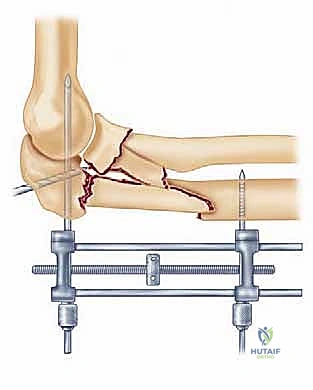

Image

TECH FIG 1 • A. A lateral radiograph with the arm in plaster shows a transverse, noncomminuted fracture of the olecranon. B. An open reduction is held with a fracture reduction forceps.